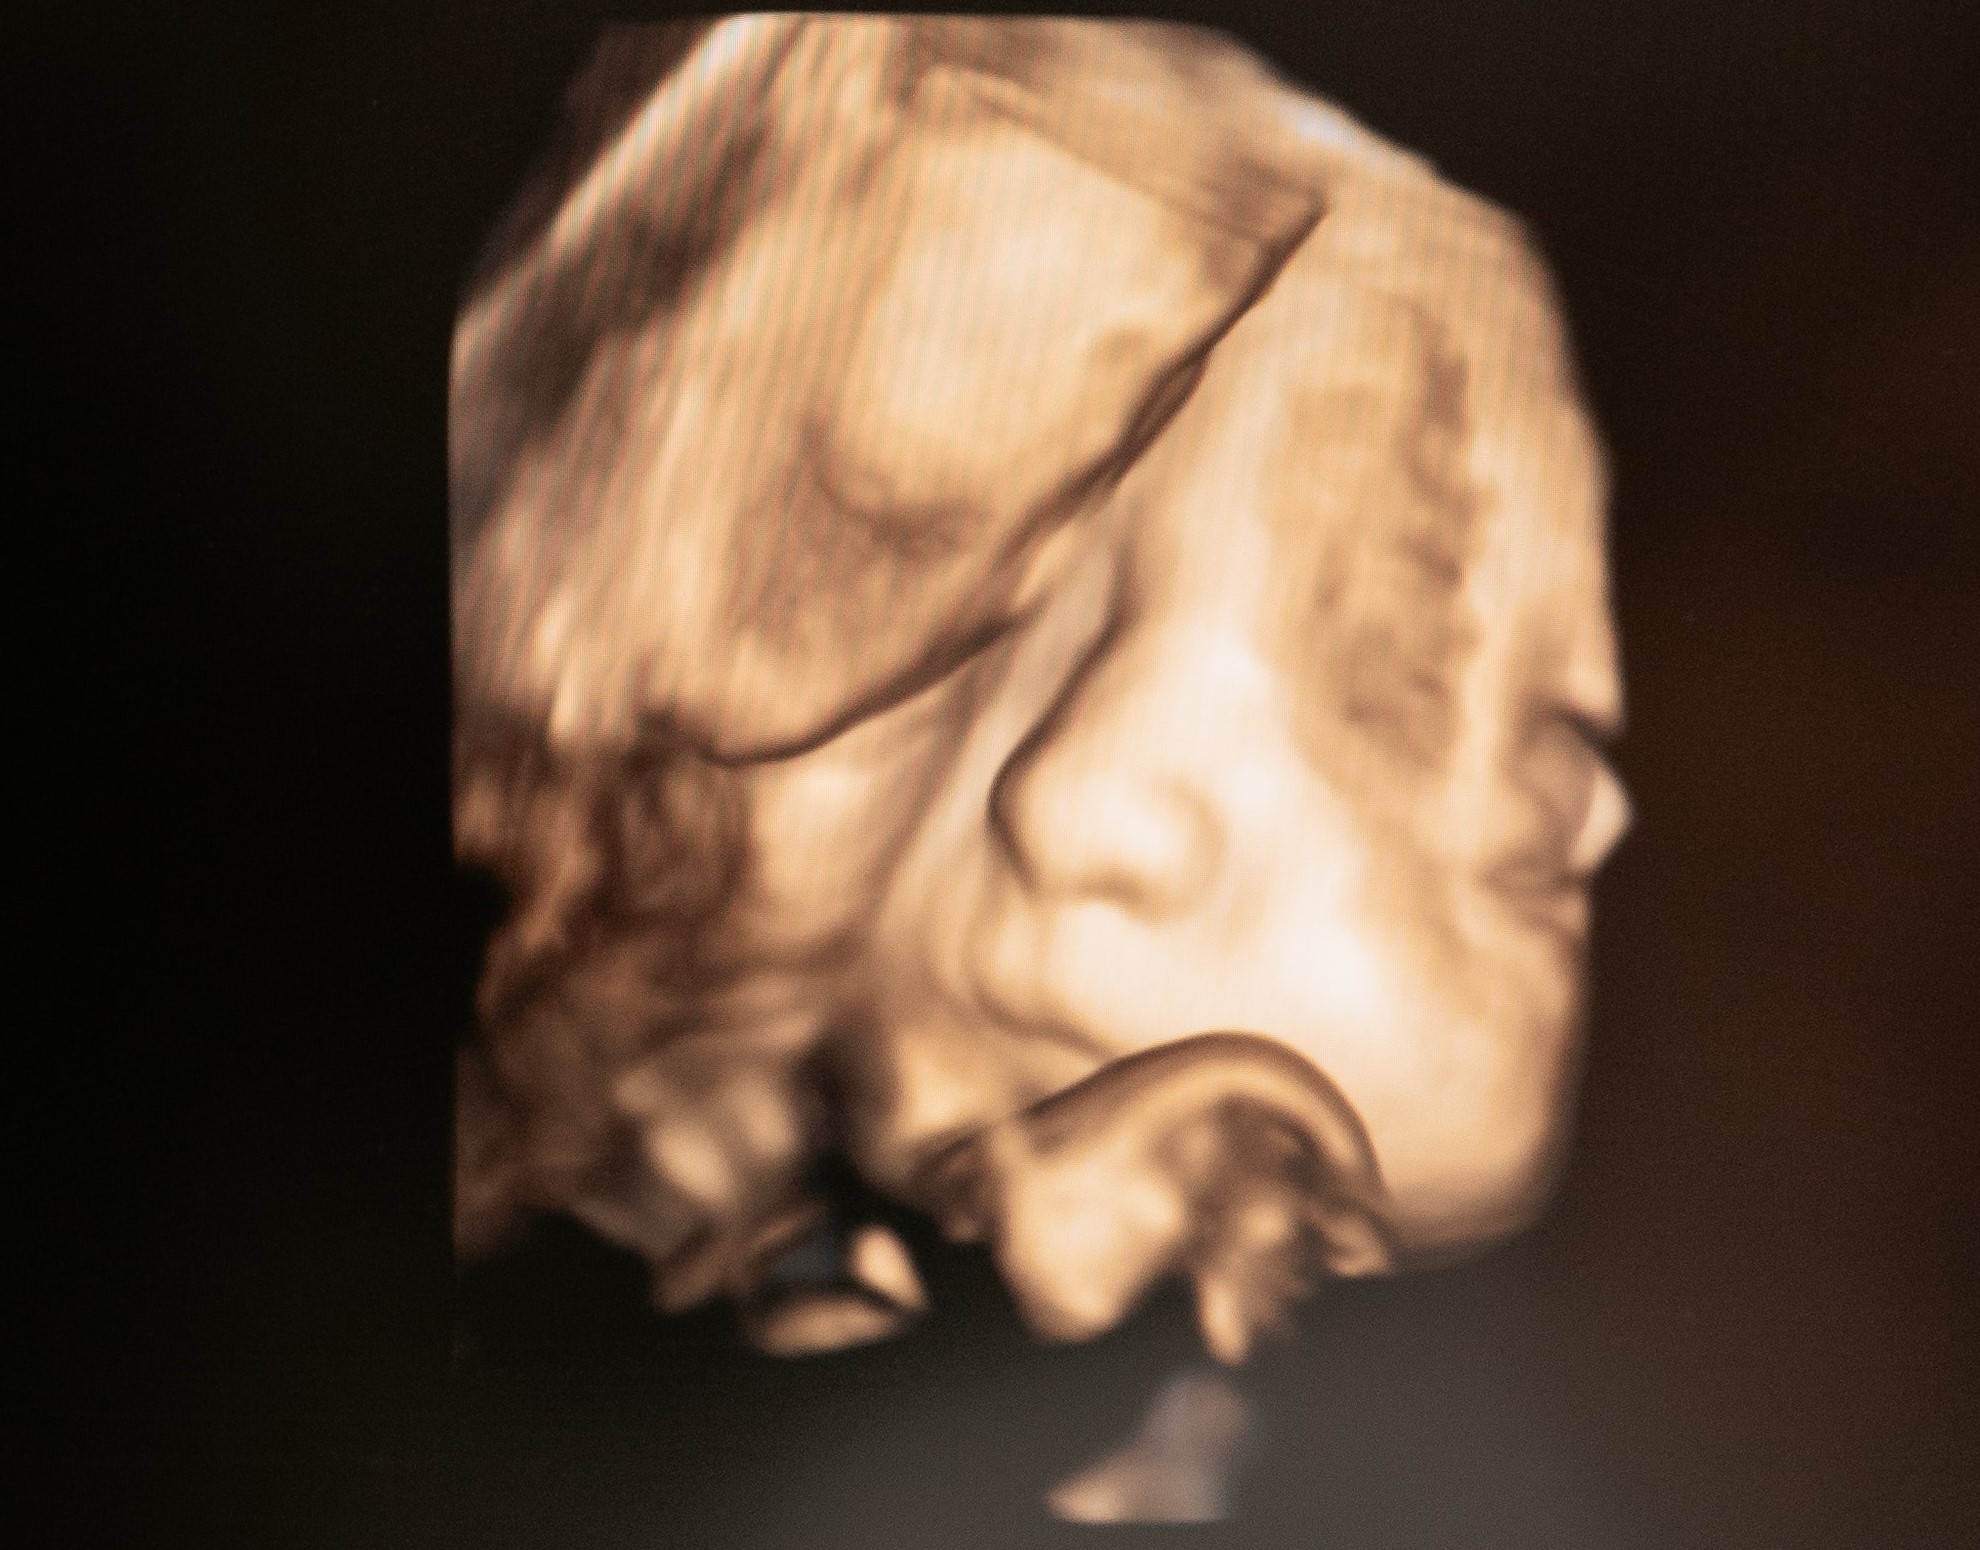

3D echo voorbeeld

3D Echo

Met 3D zie je volumineuze, bijna tastbare beelden van je kindje; 4D voegt beweging toe zodat het lijkt alsof je samen even meekijkt in de buik. Het is een feestelijk moment vol emotie.